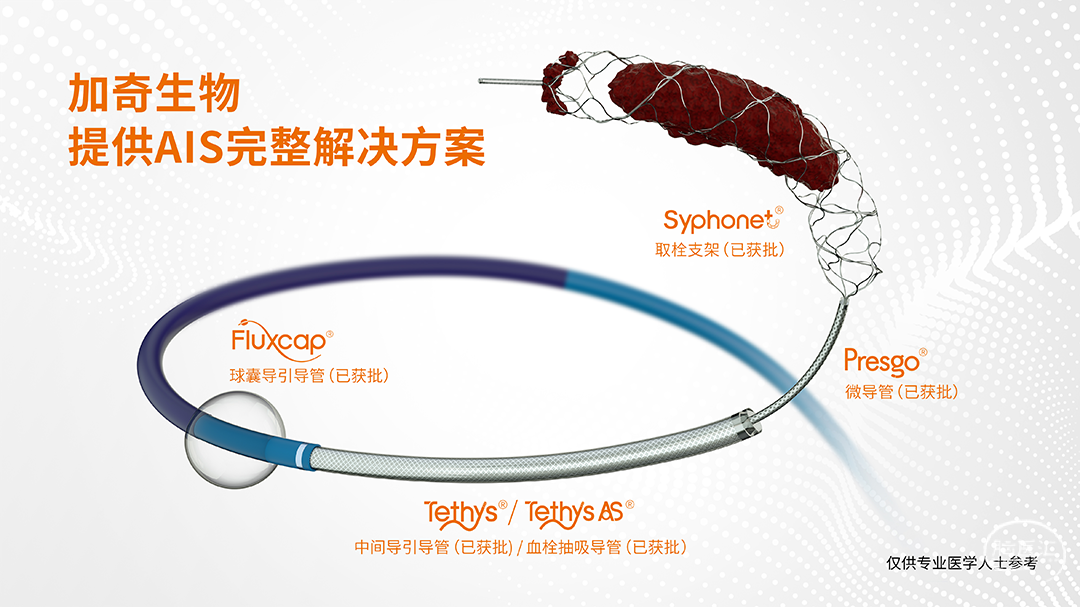

COSIS技术(颅内取栓支架保护下的慢性动脉闭塞开通术)是基于加奇生物 Syphonet®取栓支架的独特设计特点而衍生出的针对慢闭开通实施颅内保护的技术,在颅内动脉慢性闭塞,保护伞无法到位的情况下,利用Syphonet®取栓支架作为颅内的远端保护装置,减少栓子逃逸,同时利用Syphonet®取栓支架提供稳定系统,支架输送导丝完成微导管交换、球囊扩张、支架植入等操作,减少器械交换,降低并发症的发生。

加奇生物 5*35mm Syphonet®取栓支架

加奇生物 3.5*15mm SacSpeed®球囊扩张导管

为减少血栓逃逸事件的发生及对椎动脉血管的刺激,我们选取了预留中间管+Syphonet®取栓支架作SWIM取栓准备。这款支架全程显影,且头端带网篮,对球囊扩张过程中的逃逸血栓有抓捕能力,且抗折性强,迂曲血管内能保持完整管腔,内置的支架输送导丝头端柔软可避免血管损伤,在该病例中发挥了保护伞的作用。